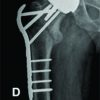

The patient then presented to ED a 2nd time, 5 days later. Unable to weight bear and now febrile. She had ongoing tenderness of her left inner thigh with some associated swelling palpable in that area. On examination, there was pain on hip flexion, internal and external rotation. Her blood results showed a highly elevated CRP of 469 and an erythrocyte sedimentation rate (ESR) of 125. She was started on IV Flucloxacillin in ED. She then underwent and MRI which showed a collection (Fig. 1, 2) in the adductor musculature of her left hip.